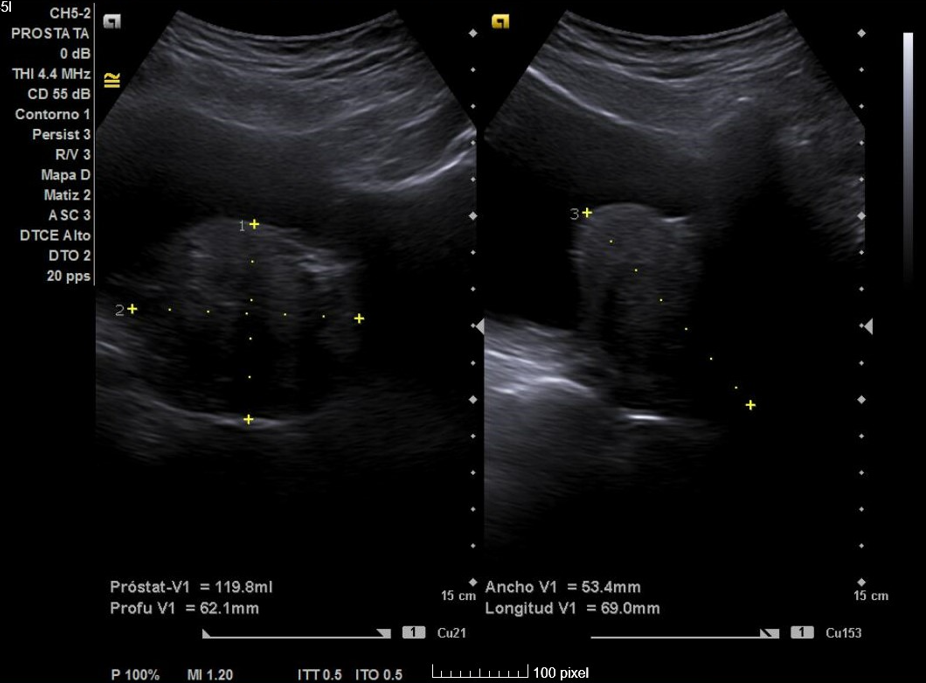

Primera ecografía: Riñón derecho de 9,6 cm, izquierdo de 9,5 cm, escoestructura y morfología normales. Vejiga con aumento de grosor de pared, residuo premiccional y posmiccional similares en torno a 350 cc (probable vejiga de lucha). Pólipo vesical a expensas de pared inferior izquierda de 18,5 x 8,7 mm. Jet ureteral bilateral conservado. Próstata de 110 cc. Se repite ecografía al mes: Pólipo vesical de 14 x 9,7 mm, próstata de 119 cc, vejiga con volumen premiccional 469 ml y posmiccional 400 ml.